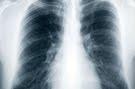

El tratamiento con irradiación craneal profiláctica mejora las tasas de supervivencia de los participantes afectados por carcinoma microcítico de pulmón, también conocido como cáncer de pulmón de células pequeñas, según un estudio dirigido por la Clínica Mayo y miembros del Grupo de la Región Norcentral para el Tratamiento del Cáncer (NCCTG), presentado durante la Conferencia Mundial sobre Cáncer de Pulmón en la ciudad de Amsterdam (Holanda). La irradiación craneal profiláctica es un tipo de radiación que se administra en el cerebro de los pacientes después de la terapia inicial (quimioterapia más radioterapia torácica) para evitar el desarrollo posterior de metástasis cerebrales.